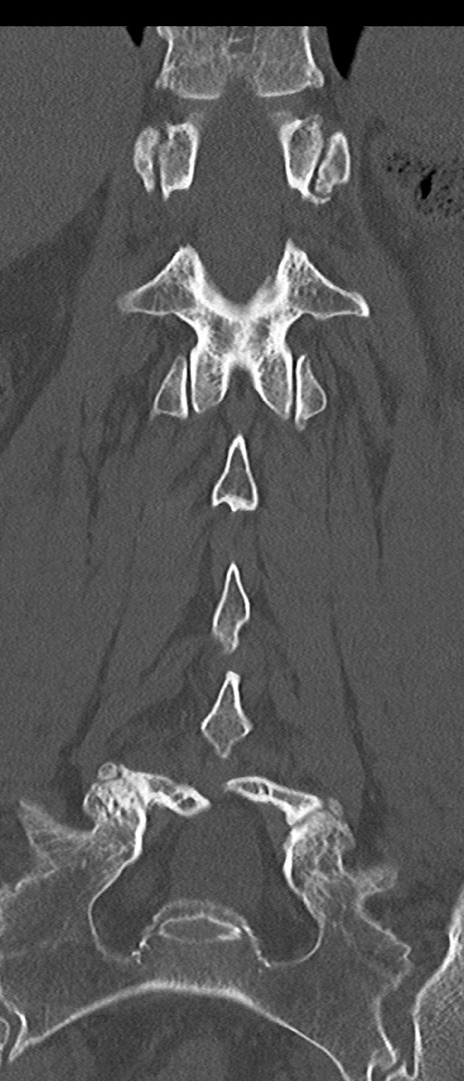

腰椎CT

横断像